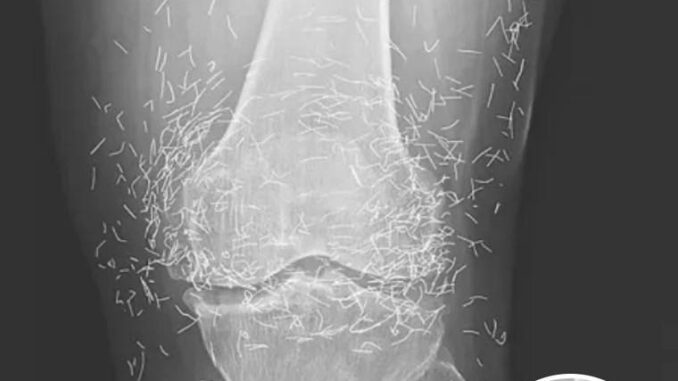

Doctors Stunned After Looking At This X-Ray Of Woman Suffering Joint Pain

A 65-year-old woman in South Korea went in for an X-ray due to severe knee pain—and doctors found hundreds of tiny gold needles embedded in her joints.

She had been suffering from osteoarthritis and turned to acupuncture after standard treatments failed. In her case, the needles were intentionally left inside her body to provide ongoing stimulation, a practice sometimes used in alternative medicine.